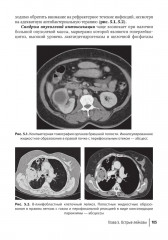

%text%